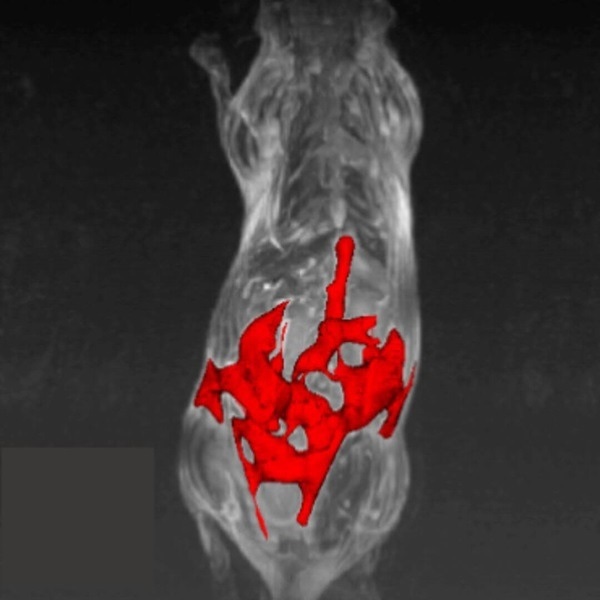

Hindlimb tumor growth: Monitoring the growth of xenograft tumor grown in the mouse hindlimb is identified with T2-weighted images. Segmentation of tumor region of interests (in red) on each tumor-containing slice allows accurate volume quantification. Image Credit: Scintica Instrumentation Inc

Monitoring the growth of xenograft tumor grown in the mouse hindlimb is identified with T2-weighted images. Segmentation of tumor region of interests (in red) on each tumor-containing slice allows accurate volume quantification. Image Credit: Scintica Instrumentation Inc